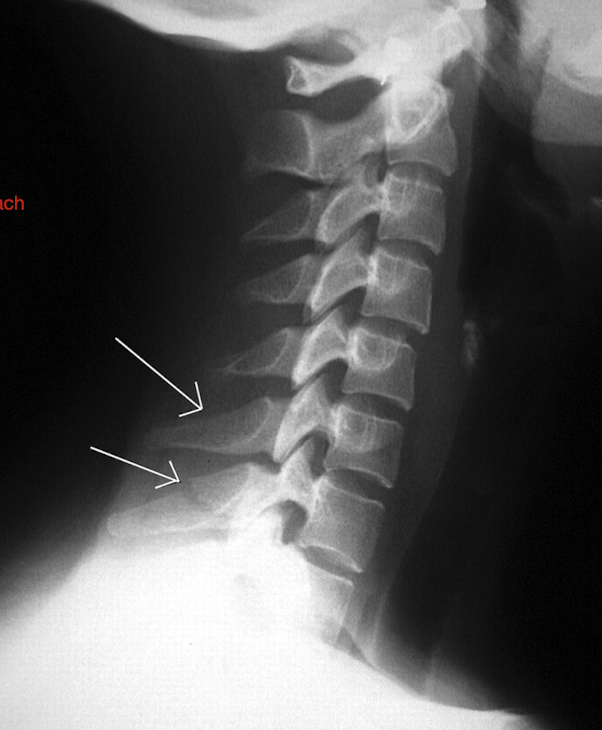

Label these 4 Lines? (C/S)

Notice: Post Vertebrae Intact, Ant Vertebrae w Fx